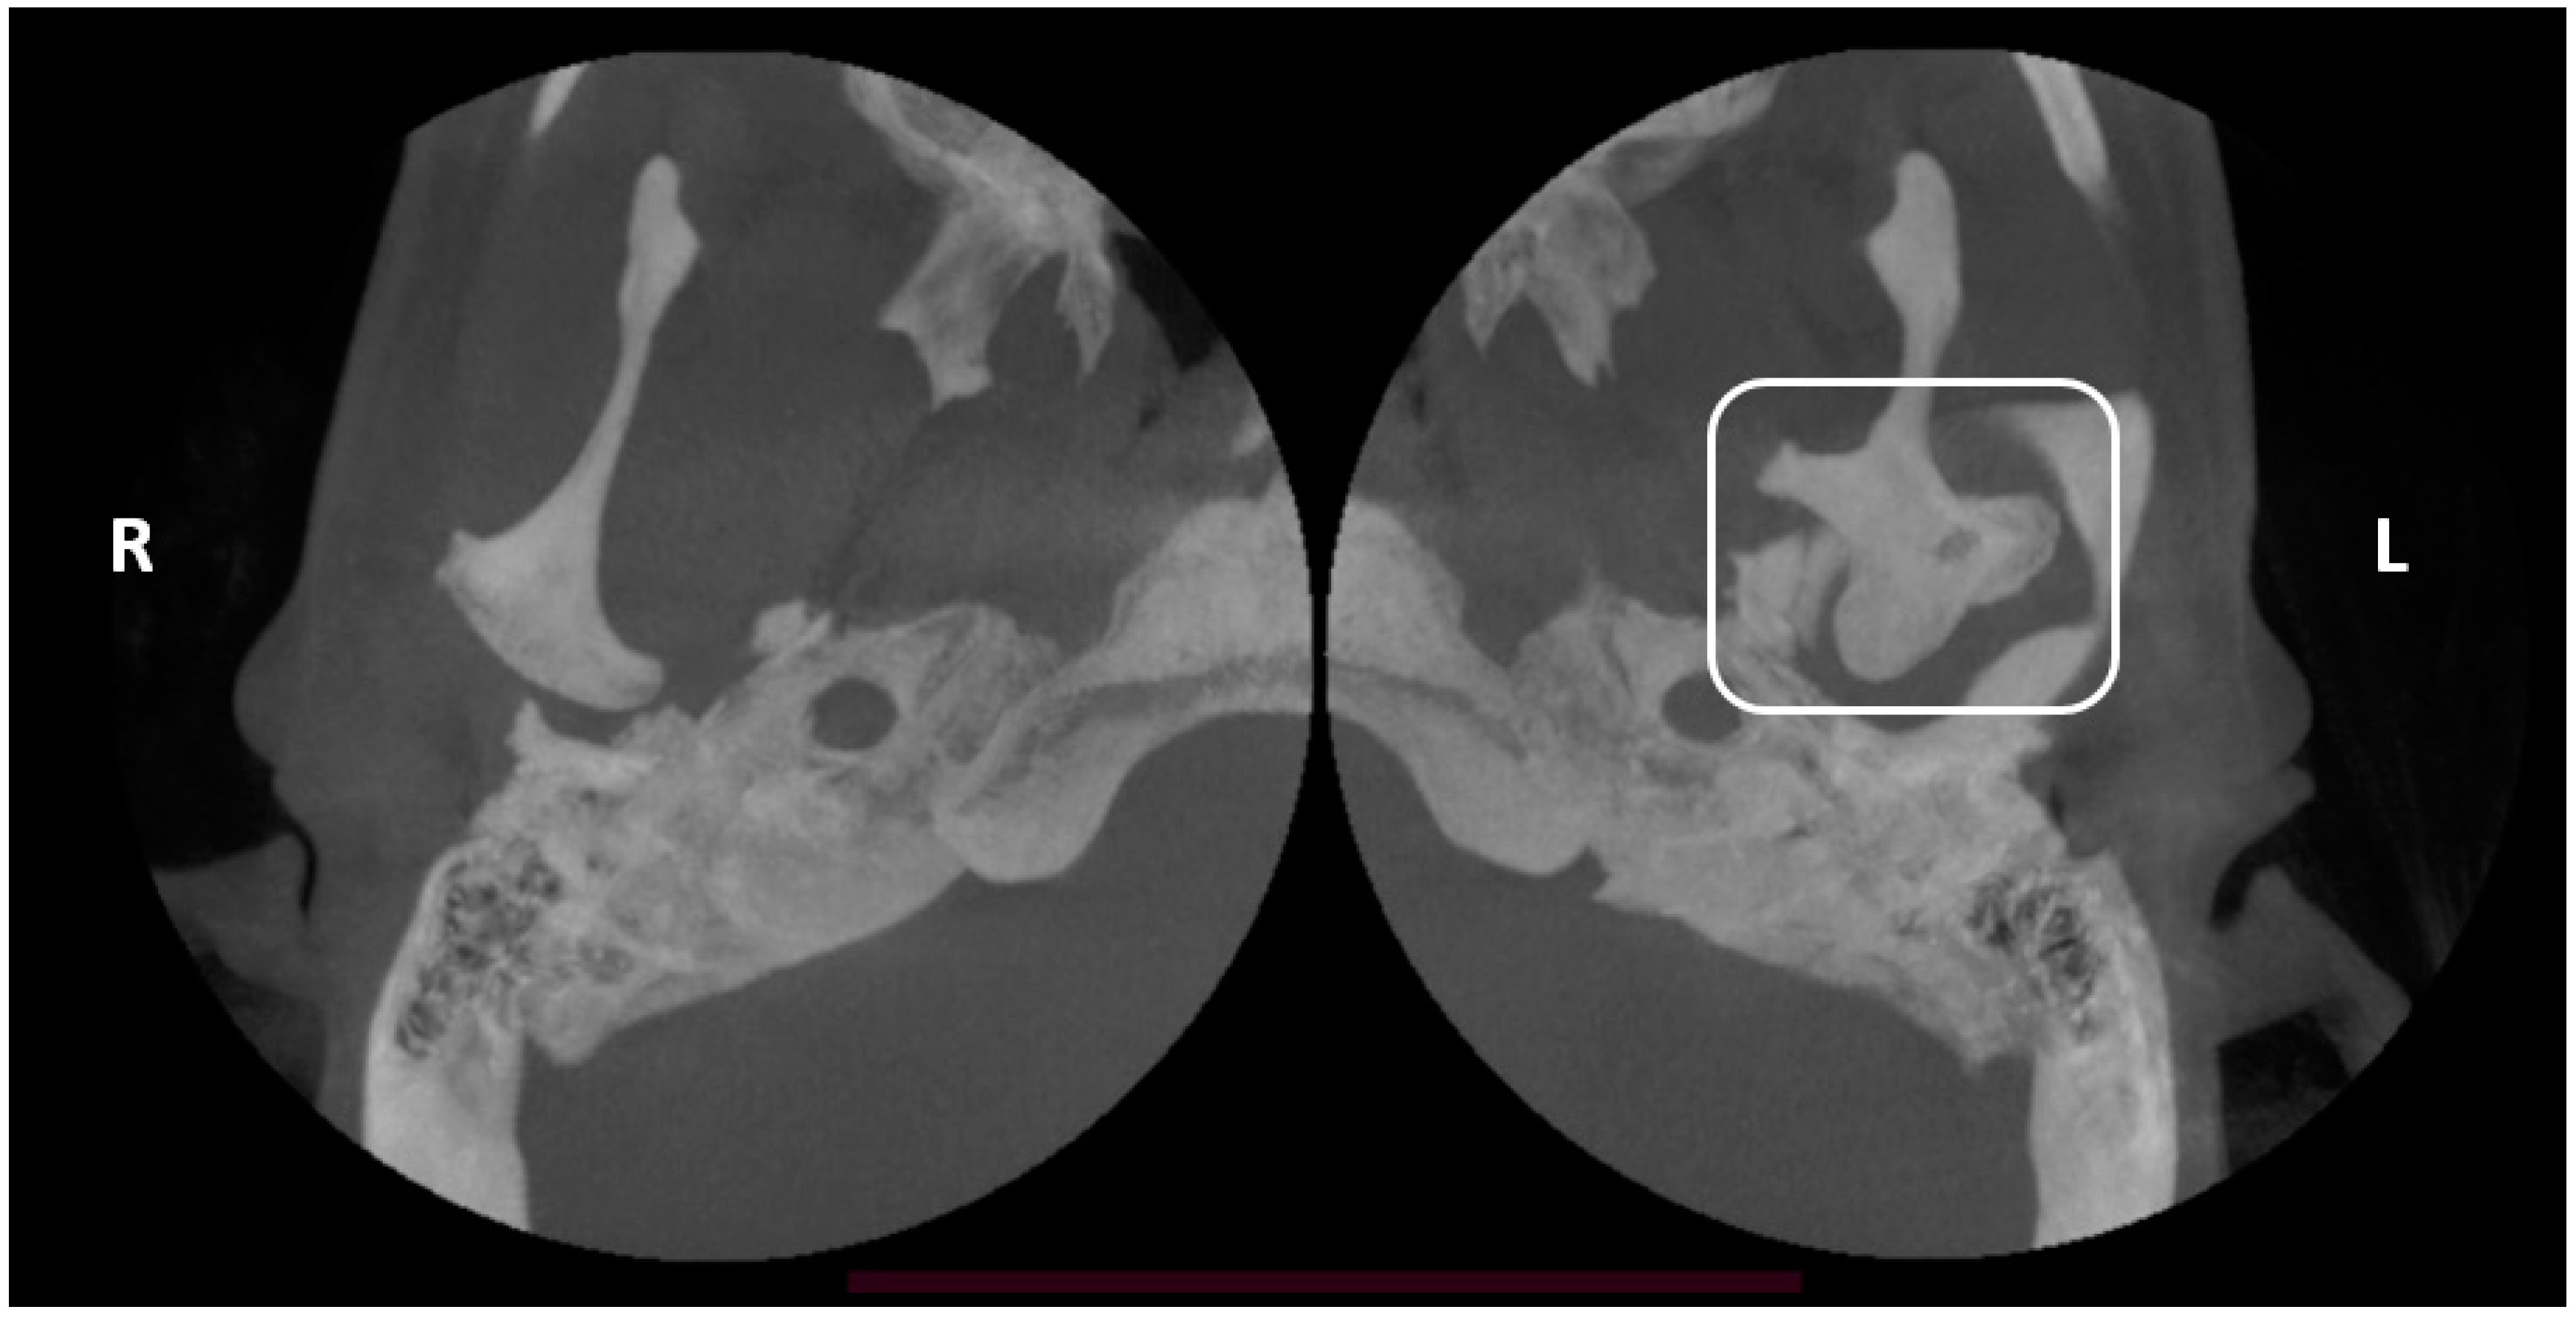

Trifid Mandibular Condyle: Case Report and Current Review of the Literature

2. Case Report